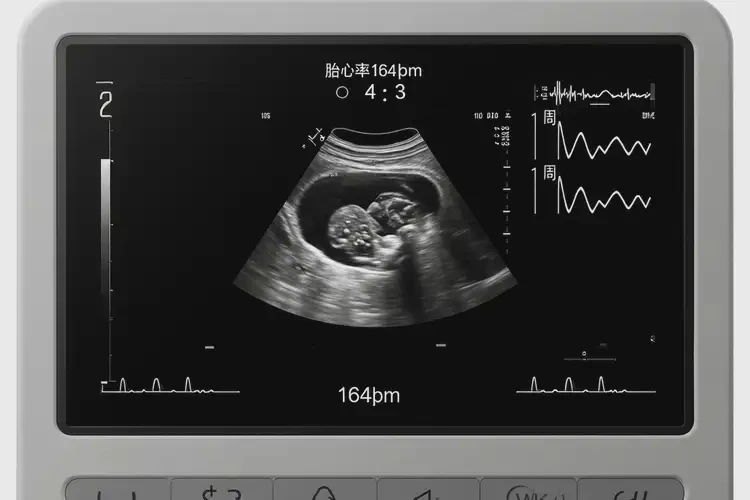

懷孕第2周胎心164還能保住嗎

胎心164次/分鐘在懷孕第2周屬于正常范圍,通常無(wú)需過(guò)于擔(dān)心。

在懷孕第2周,胎心率在120-180次/分鐘之間都被認(rèn)為是正常的。胎心率的波動(dòng)受到多種因素的影響,包括胎兒的活動(dòng)、孕婦的情緒和身體狀況等。單次胎心測(cè)量結(jié)果為164次/分鐘,并不能直接說(shuō)明胎兒是否能保住。

懷孕第2周胎心164還能保住嗎(圖1)